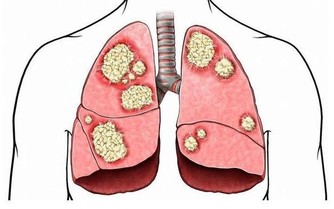

夏季染病,大都當即發作,故有“六月債,還得快”之說。但有一種病是有所潛伏,到秋季才發作,如延至冬季就很嚴重了!——這就是“心病”。也即《內經》所說的“此夏氣之應,養長之道也。逆之則傷心,秋為痎瘧,冬至重病”。但必須說明的是這裡說的“心病”,並非是指現代醫學上的“心血管病”,而是指精神方面的有關“神誌、情志”的病(古書上所提及的“心” ,實際上是相當於今天人們常說的“精神”)按中醫的“五行”說,夏季是“火旺(夏主心,夏天心火很旺)、土相(脾胃處於'盛'的地位)、木休(肝處於相對的'休養'狀態)、水囚(腎易'虧')、金死(肺易'虛')”。心“火”一“旺”,“火克金”,所以容易造成“肺(金)虛”;本是“腎水”克“心火”,而“心火”很“旺”時,就容易出現“心火”對“腎水”的“反侮”現象,故“腎水”易“虧”。

三是補養肺腎。中醫認為,按五行規律,夏天心火旺而肺金、腎水虛衰,要注意補養肺腎之陰。可選用枸杞子、生地、百合、桑葚以及酸收肺氣藥,如五味子等,可防出汗太過,耗傷津氣。